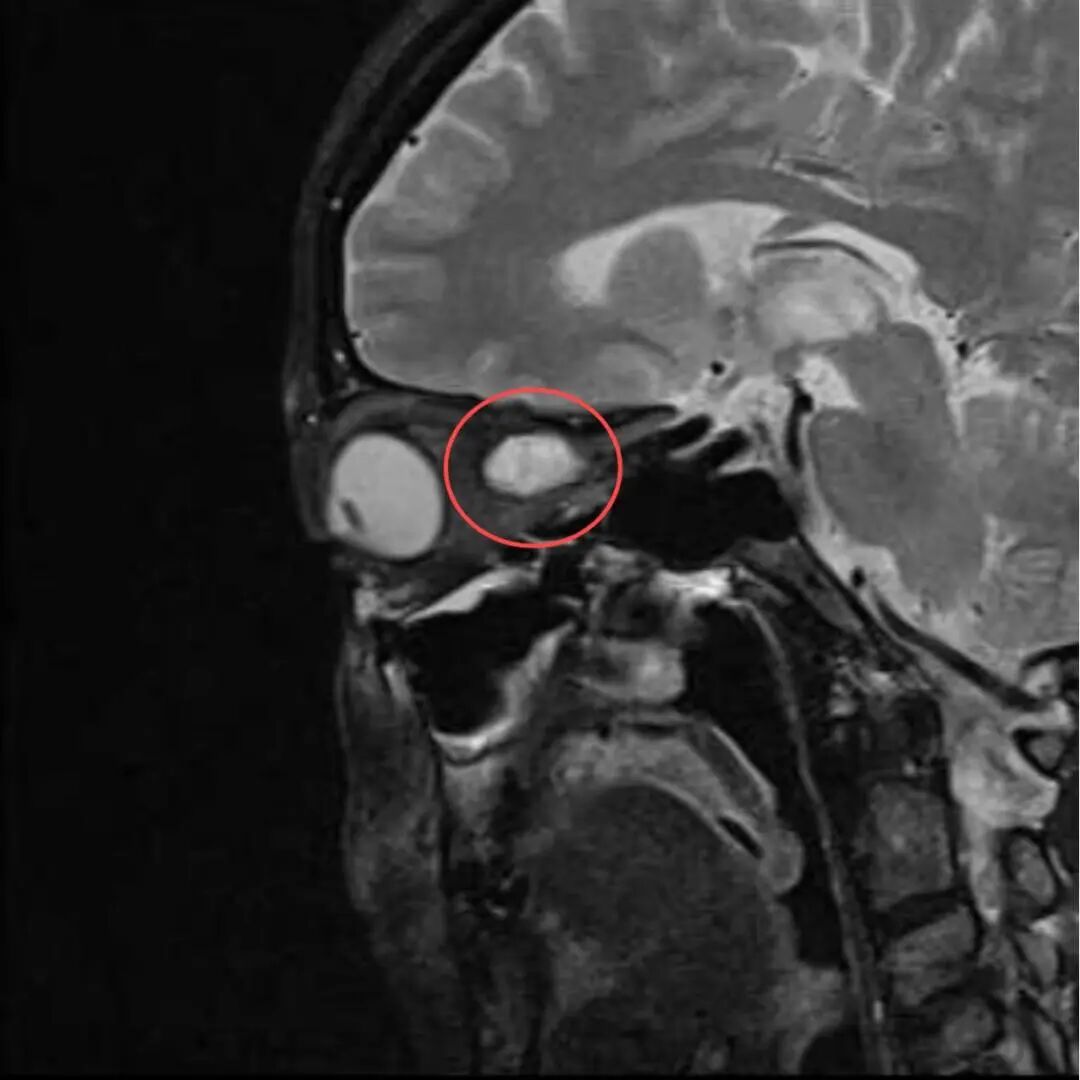

多年来,贵州航天医院各科室紧跟医学前沿,不断强技术、补短板,大力开展新技术、新项目,完成了许多高精尖、高难度、本地区“首例”的技术,填补了医院医疗技术空白,满足了群众日益增长的医疗需求。 案例分享 患者在两年前无明显诱因出现左眼胀痛、左眼视力下降等症状,由于当时患者自感不太严重,未予重视,随着时间的推移,症状逐渐加重,遂前来我院就诊,为更好的为患者进行诊治,收入了耳鼻喉科。经眼科查体显示:VOD(矫正视力)→1.0,VOS(矫正视力)→1.0,进行眼眶平扫+MRI检查后,初步诊断为:左眼球后脂肪间隙内占位,考虑良性病变,血管瘤可能。 考虑到患者病情复杂,耳鼻喉科组织眼科、麻醉科等科室开展了多学科联合会诊,对患者病情、既往病史等进行了全面深入的综合分析研讨,制定了鼻内镜下左侧鼻窦功能开放术+左侧眶内肿瘤切除术的方案,由于手术难度较大,在充分告知手术风险及并发症等相关信息后,患者及家属同意手术。经过充分的术前准备,耳鼻喉科借助经鼻内镜,成功通过鼻窦经由筛窦眶纸板、蝶窦外侧壁将肿瘤完整切除,最大程度地保护了眶内的血管、神经等重要组织。 术后,患者未出现视力减退、视野缺损等并发症,仅眶周稍青紫肿胀和轻微复视。患者2周后复查,复视症状、眶周青紫肿胀消除,术后MRI(眼眶平扫+增强扫描)显示左眶内肿物已消失。 该技术的开展,特别邀请了中山大学附属第一医院耳鼻喉科专家左可军教授莅临主刀,并对该技术的实施进行指导,已成功完成多例鼻眼相关内镜手术,解决了患者外出就医难、排队时间长、花费多等难题,让广大民众在家门口享受到了优质的医疗服务资源。 什么是鼻内镜下经鼻腔、 鼻窦进路眶内肿物切除术 眼眶是一个狭小的解剖间隙,结构复杂,功能重要,周围临近组织较多,含有许多重要结构,眶深部的肿瘤切除手术难度大,容易侵犯神经,出现视力丧失等并发症。随着眼-鼻相关学科发展和微创理念的深入,鼻内镜内侧开眶入路得到显著发展和应用,鼻内镜下经鼻腔、鼻窦进路眶内肿物切除术,具有微创、直视、并发症少等优势,目前已成为眶内肿物切除首选手术进路,主要应用于泪道系统疾病、眶骨折修复、眼眶内侧肿瘤切除、眼眶减压、海绵状血管瘤切除等。 鼻内镜下经鼻腔、鼻窦 进路眶内肿物切除术原理 手术基于先进的鼻内镜设备,通过鼻腔入路直接对眼眶及其毗邻区域进行操作,鼻腔与眼眶相邻,眼眶内侧壁主要由筛骨纸板构成,骨质菲薄,很容易经此进入眼眶,所以鼻腔可作为合适的手术通道,让操作更精准、更微创,同时,内镜下经鼻眼眶手术可利用该通道实现面部无切口。 鼻内镜下经鼻腔、鼻窦 进路眶内肿物切除术优势 ✔肿物可完整切除,较好的保护视力。 ✔可避免眼外部入路及经颅开眶入路的头面部切口。 ✔无脑组织的牵拉损伤,对眼内容物的牵拉损伤较小。 ✔经鼻切口外形无改变,术中组织结构放大、视野清晰,肿物分离更便捷。 贵州航天医院耳鼻喉科专家团队 左可军 中山大学 附属第一医院耳鼻咽喉科 贵州航天医院耳鼻喉科 特聘教授 医学博士 硕导 主任医师 临床擅长:鼻科、鼻眼相关外科、鼻颅底相关外科以及鼻变态反应科的临床和基础工作。 南方青年鼻科联盟创始人,担任中国医师协会耳鼻咽喉科分会整形美容学组委员、海峡两岸医药卫生交流协会眼科学专业委员会眼科内窥镜微创手术学组委员、广东省精准医学应用学会头颈肿瘤分会副主委、广东省中西医结合学会耳鼻咽喉科分会副主委、广东省眼健康协会眼与全身疾病专业委员会常委。获得国家二级运动员和南粤优秀研究生称号,2018年荣获“广东医院最强科室之实力中青年医生”,2020年荣获全国卫生健康系统抗疫先进集体、中国医师协会耳鼻咽喉头颈外科分会抗疫先进个人,2021年荣获广东省科技进步一等奖,2023年荣获第七届“羊城好医师”。 张光进 耳鼻喉科主任 副主任医师 临床擅长:对耳鼻喉头颈常见病的诊治具有丰富的临床经验,擅长鼻内镜、耳内镜、耳显微、头颈咽喉部肿瘤及眩晕手法复位等的诊疗。 曾先后前往第三军医大学西南医院、复旦大学耳鼻喉科医院、上海新华医院及北京友谊医院进修学习;遵义市医学会常务委员;主持及参与级科研课题2项,发表专业论文10余篇。 陈维信 耳鼻喉科 主任医师 临床擅长:对耳鼻喉科常见疾病的诊治具有丰富的临床经验,擅长耳、鼻、喉及头颈部位的手术。 曾先后前往上海交通大学附属仁济医院耳鼻喉-头颈外科、北京大学人民医院耳鼻喉-头颈外科参加鼻内镜外科进修学习。中国睡眠研究会委员,贵州省医学会耳鼻喉-头颈外科学分会委员,贵州省耳鼻喉-头颈外科学会理事,贵州省医学会变态反应学分会委员,贵州省防聋治聋技术指导组专家,遵义市耳鼻喉科分会副主任委员,遵义市医疗事故鉴定专家库成员;主持省部级科研课题2项,发表专业论文20余篇。 秦 晋 耳鼻喉科 副主任医师 临床擅长:对耳鼻喉科常见疾病的诊治具有丰富的临床经验,擅长耳、鼻、喉及头颈部位的手术。 遵义市医学会常务委员;曾先后在第三军医大学西南医院、湖南湘雅鼻颅底培训班进修学习。 贵州航天医院耳鼻喉科简介 基本情况 贵州航天医院耳鼻喉科拥有一支经验丰富、技术精湛的医疗团队,共有医师9名,其中副高级以上专家5名,医学硕士2名,开放床位20张,拥有德国WOLF鼻窦内窥镜系统、日本奥林巴斯电子喉镜、奥林巴斯电子鼻咽镜、丹麦临床听力监测设备、声导抗仪、听觉诱发电位、耳声发射仪、美国杰西低温等离子治疗仪、杭州好克鼻窦内窥镜系统、鼻动力系统、耳显微镜、耳用电钻、微波治疗仪等先进设备。 专科特色 (一)耳部疾病 耳内镜下胆脂瘤切除术、III型鼓室成形术+人工听骨听骨链重建术。 (二)鼻部疾病 内镜下鼻息肉切除术、鼻窦功能开放术。 (三)咽喉疾病 内镜下扁桃体、腺样体低温等离子切除术。 (四)交叉学科 1.经鼻内镜下眶内肿瘤切除术 2.经鼻内镜下鼻腔泪囊吻合术 诊疗范围 (一)常见耳疾的诊断和治疗:中耳炎、耳聋、耳鸣等。通过各种耳科检查手段,如耳镜检查、听力测试和耳脑干听觉诱发电位检查等,准确诊断患者病情,制定个性化治疗方案。 (二)鼻炎、鼻窦炎、鼻出血等鼻科疾病的诊断和治疗:采用微创技术,如鼻内窥镜检查、低温等离子手术等,为患者提供有效的治疗方案。 (三)喉炎、声带息肉、声带白斑等喉科疾病的诊断和治疗:通过声带电子镜、喉镜等设备,准确判断患者的喉部病变,为患者提供精准的治疗方案。 (四)鼻眼、鼻颅底相关手术。